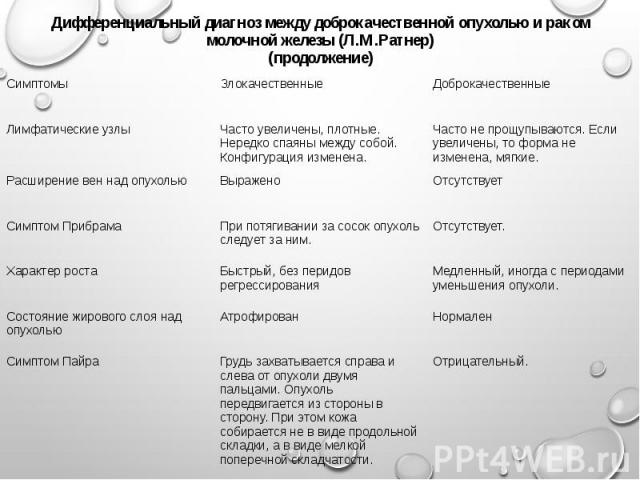

Обратитесь к врачу для точной диагностики и исключения злокачественных образований.

Следуйте рекомендациям врача по дополнительным обследованиям, таким как УЗИ или маммография.